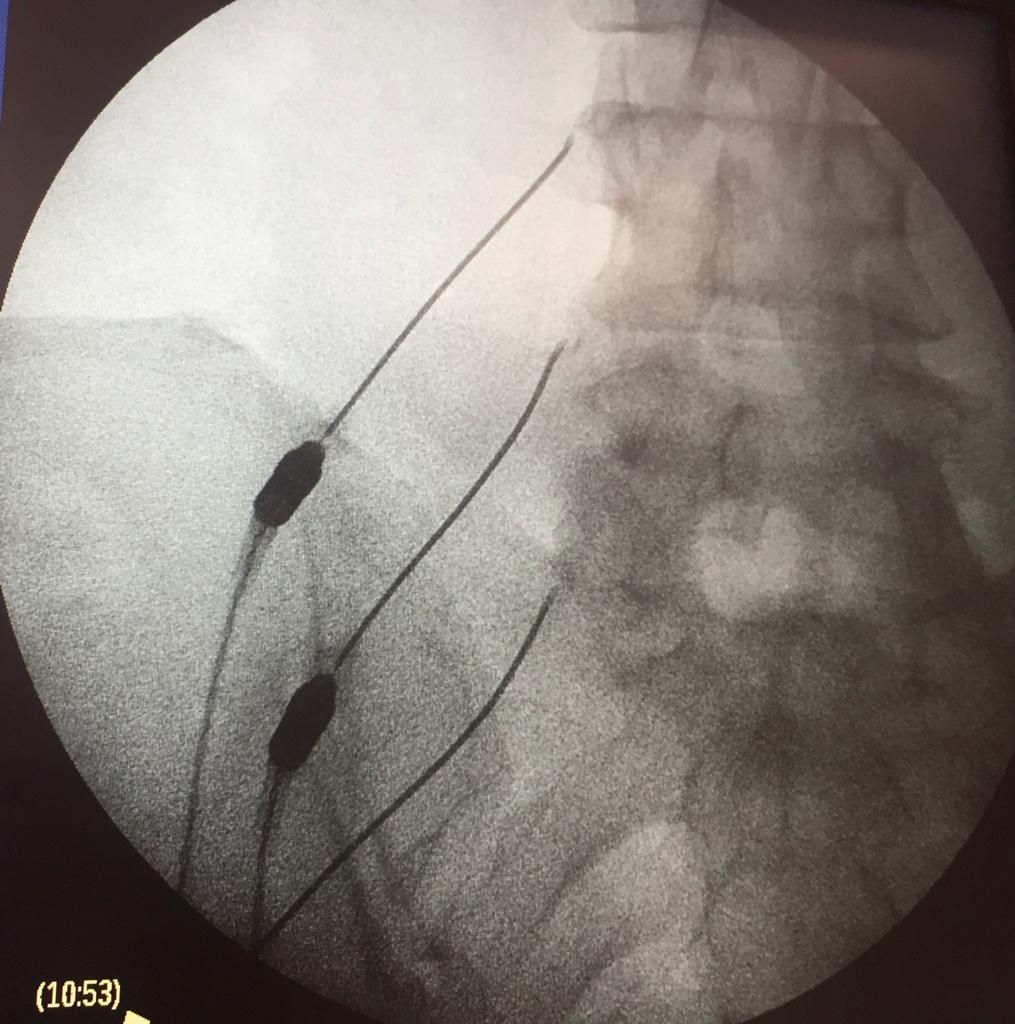

Implante de dispositivos intratecales para manejo de dolor

06/12/2024